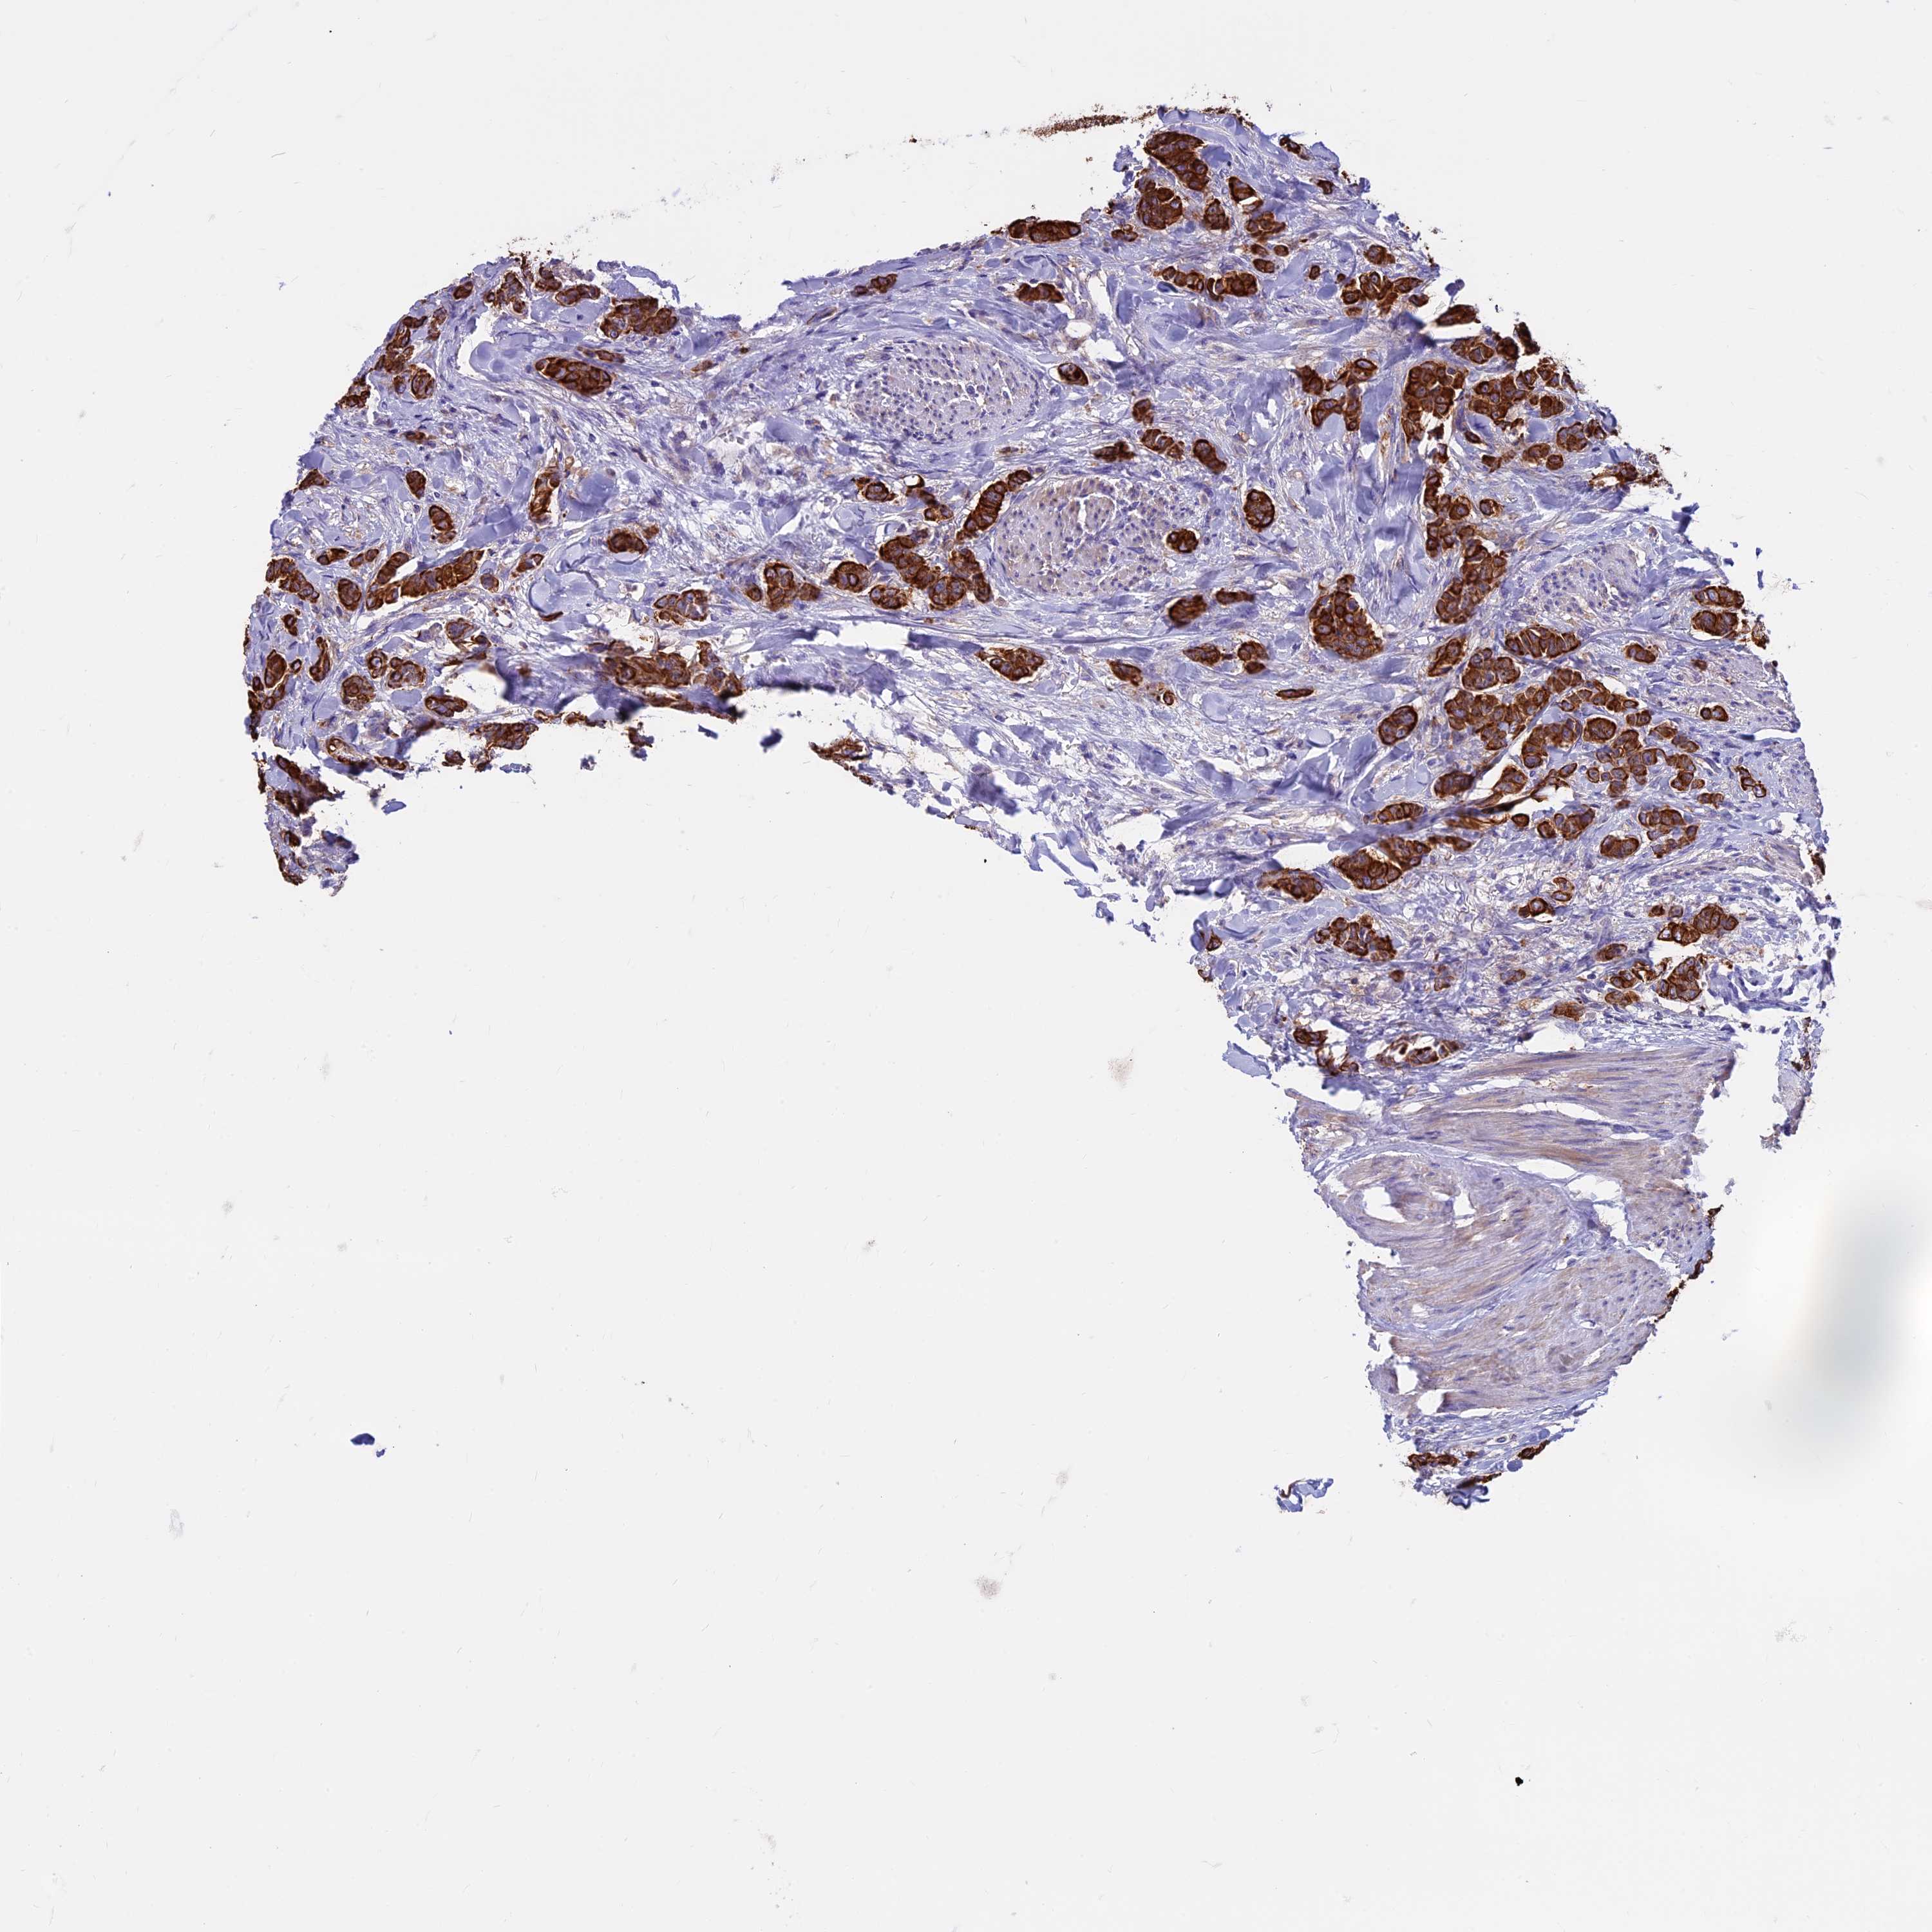

CANCER BREAST CANCER Show tissue menu

BRCA TCGA BRCA VALIDATION PROTEIN EXPRESSION

Breast cancer

Human cancer